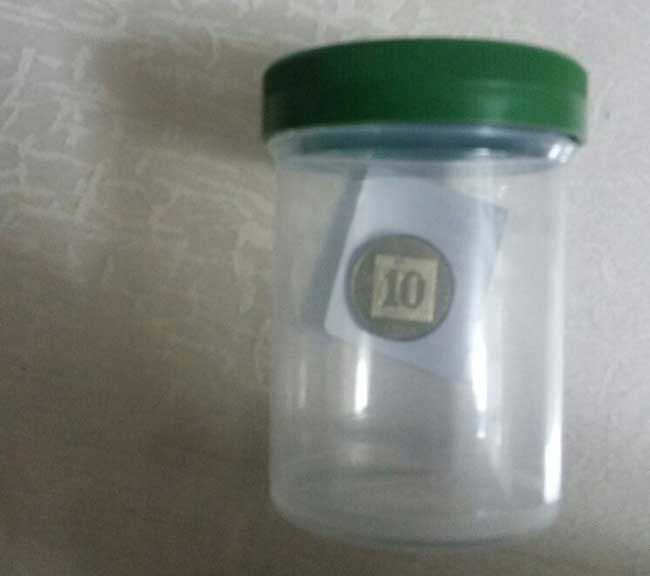

הצוות הרפואי במוקד של מכבי שירותי באשדוד כבר חשבו שראו הכל, אך הם נדהמו למצוא מטבע של 10 אגורות בוושט של ילדה בת ארבע ביום חמישי האחרון.

הילדה הגיע בבית החולים אסותא באשדוד והוכנסה בבהילות לצילום חזה, ותוך זמן קצר ולאחר בדיקות נוספות, הועברה לחדר הניתוח. במהלך הניתוח הוחדר צינור אופטי לוושט, על מנת לשלוף את הגוף הזר – והמטבע יצא בשלמותו. לאחר הניתוח אושפזה הילדה במחלקת כירורגית לילדים וביום למחרת שוחררה לביתה.

לדברי ד"ר אראלה רוטלוי, מנהלת מחלקת האינטגרציה בבית החולים אסותא אשדוד במכבי שירותי בריאות: "מדובר במקרה חריג, של גוף זר שנתקע בוושט של ילדה קטנה, המטבע היה גדול יחסית ועל כן נתקע ולא ירד בוושט. לשמחתנו הרבה, המקרה הסתיים בצורה הטובה ביותר, אך חשוב לחזור ולהדגיש בפני ההורים כי הרחקת חפצים קטנים מהישג ידם של תינוקות וילדים קטנים היא חיונית, משום שבליעתם עלולה לגרום לנזק משמעותי".